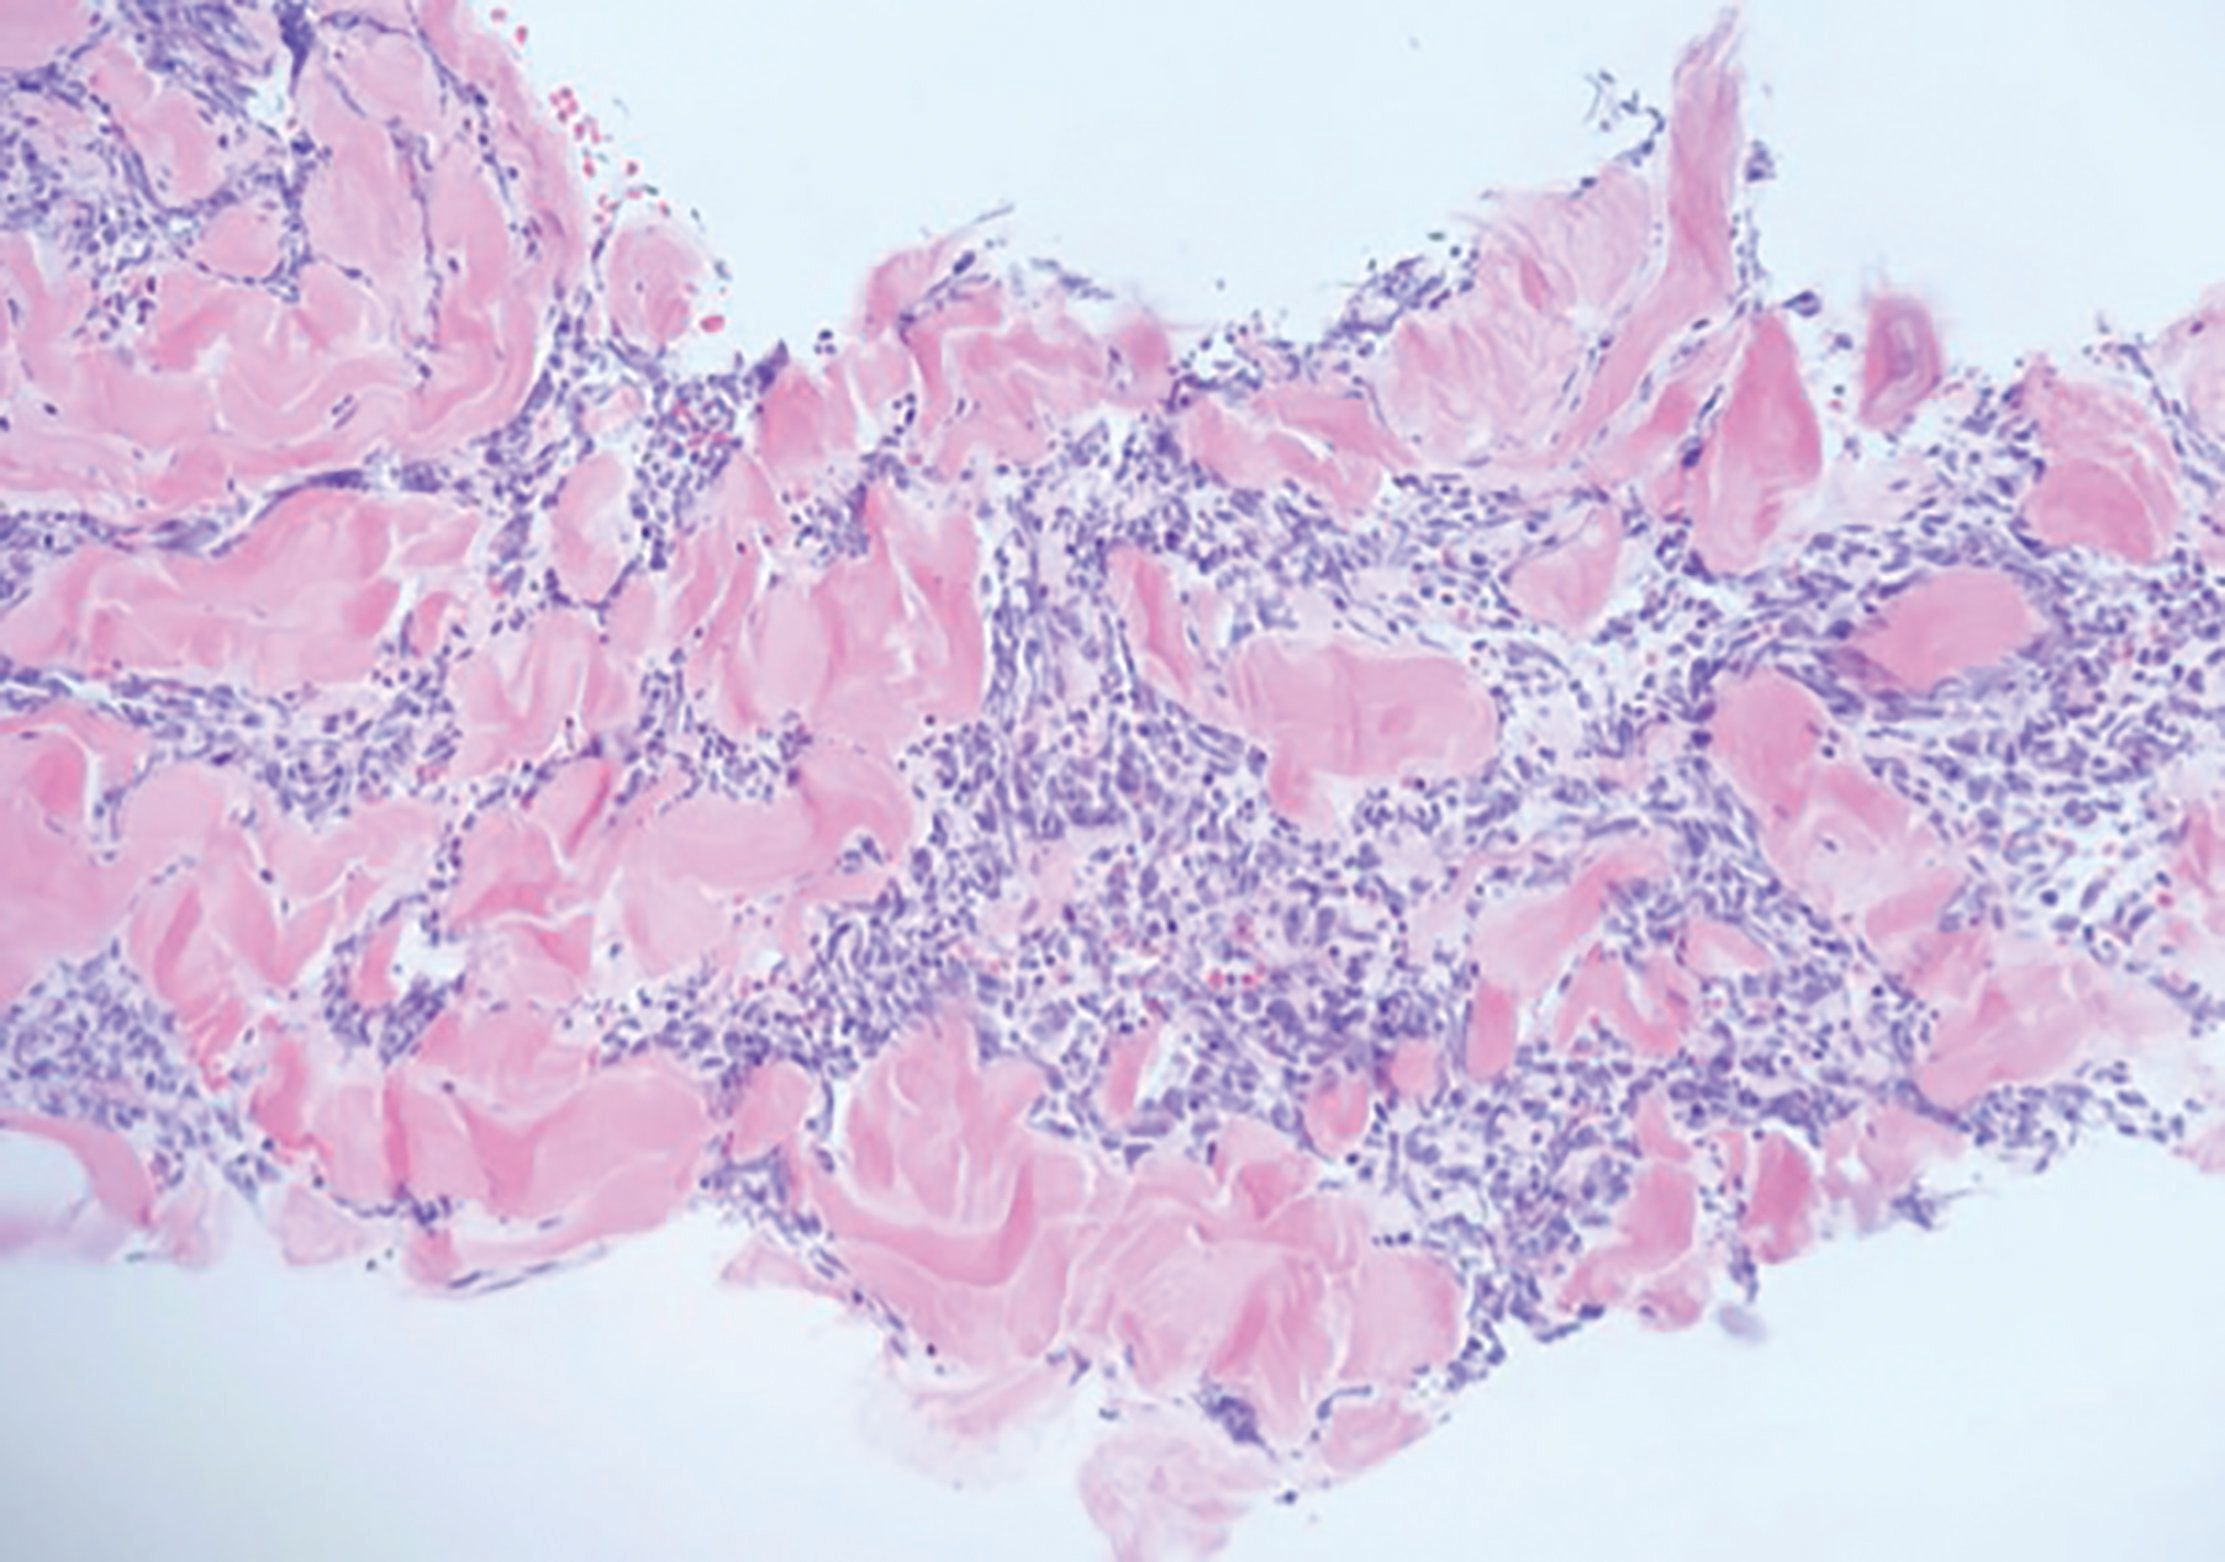

乳房结节活检的组织病理学见(图3)和(图4)。

图3

图4